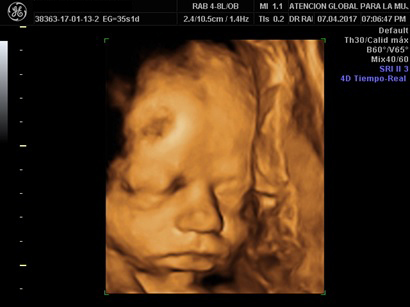

Ultrasonidos

Las unidades de ultrasonido están equipádas con equipos 3D / 4D de última generación para garantizar los servicios tecnológicamente más avanzados.

El ultrasonido 3D / 4D de última generación para ofrecer el más alto nivel de presición en imágenes de ultrasonido así como sus diversos tipos dependiendo de las semanas de gestación.